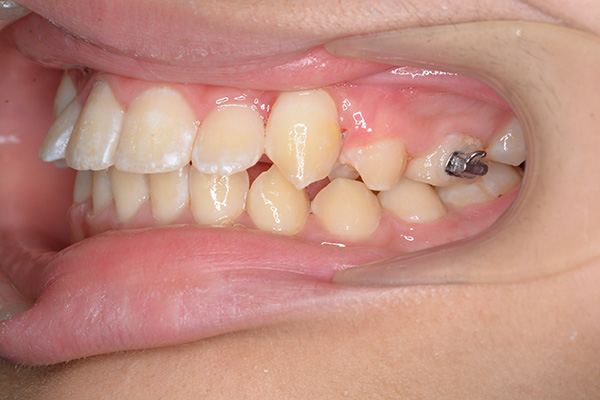

| 口腔内所見 | over jet 5.5mm,over bite 5.0mm,大臼歯関係はⅠ級 、Hellmanのdental ageはⅢBであり上突歯列を呈していた。 |

| セファロ所見 | Sellaに対して下顎頭は後方位だが下顎骨は大きくしっかりとした形態をしており前後的にはⅠ級、垂直的にはロウアングルの骨格形態をしていた。 上顎前歯は唇側傾斜を呈していた。 |

| パノラマ所見 | 上顎左右側犬歯は近心傾斜し側切歯歯根に重なるように認められた。 |

| 批評・予后 | 埋伏歯の牽引を行い位置異常の改善をした結果、適切な犬歯のガイドが得られ、ほぼ緊密な咬合となったように思う。口元の改善を希望された場合は小臼歯抜歯症例として本格矯正治療を行う予定である。 |